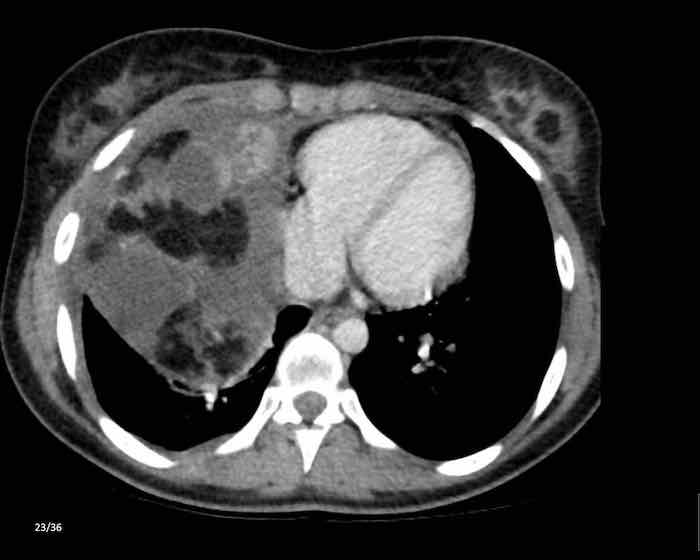

Các hình ảnh này của một nam giới 71 tuổi.

Trên CT ngực, tình cờ phát hiện một khối ở tuyến ức.

Hãy phân tích các hình ảnh. Nhận định của bạn là gì?

Hình ảnh

Một phần tổn thương có ngấm thuốc cản quang và có một số vôi hóa, có thể nằm ở thành nang.

Khi một tổn thương tuyến ức có thành phần đặc, nguyên tắc là… “khi còn nghi ngờ, hãy phẫu thuật cắt bỏ”.

Tổn thương đã được phẫu thuật cắt bỏ dựa trên kết quả CT và kết quả giải phẫu bệnh cho thấy đây là u tuyến ức dạng nang.